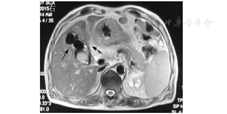

入院后体格检查:血压122/73 mmHg(1 mmHg=0.133 kPa),体温为36.8 ℃,心率为83次/min,呼吸频率为21次/min,皮肤和巩膜轻度黄染,心肺未见异常,右上腹压痛,无肌紧张,无反跳痛,墨菲征阴性。血常规示血白细胞计数为10.9×109/L,血红蛋白为120 g/L。肝功能检查示ALT为57 U/L,AST为28 U/L,GGT为214 U/L,TBil为23.90 μmol/L,DBil为19.1 μmol/L,凝血功能、肾功能、血电解质、粪便常规和尿常规等均正常,胸部X线片和心电图均正常。考虑患者为胆囊结石、胆囊炎可能性大,但需排除胆总管结石,遂行腹部超声、CT和磁共振胰胆管造影(magnetic resonance cholangiopancreatography, MRCP)检查。腹部超声检查提示为胆囊结石(填满型);CT检查提示胆囊异常强化灶,考虑肿瘤性病变、胆囊结石,胆囊与结肠密切相连,见图1;MRCP检查提示胆囊多发结石并发胆囊炎,胆囊壁增厚,胆囊与结肠紧密相连,见图2;故诊断为胆囊结石伴急性胆囊炎或胆囊肿瘤,遂拟行腹腔镜胆囊切除术。